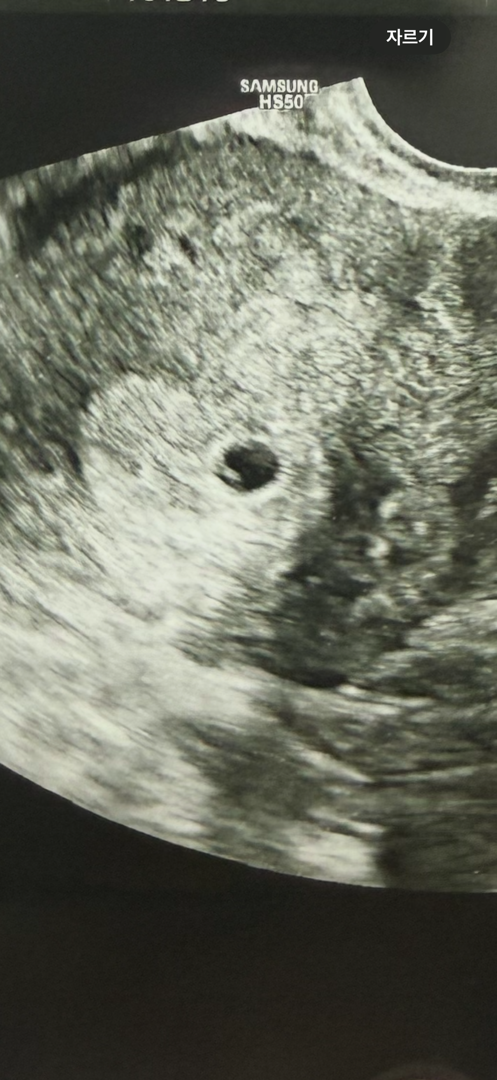

막생 기준으로 오늘이 5주 6일 되는 날입니다. 오늘 병원에서 본 초음파에는 아기집은 확인되고 난황이랑 아기는 안보인다고 하시는데 아기집 안에 있는 저 하얀게 뭘까요? 주수는 5주 2일로 수정해주셨어요..

이제 5mm 정도 됐다고 하셨어요!

저게 난황 아닌가요??? 저도 5주1일에 아기집보구 저렇게보이는게 난황 추정이라 하셨거든요!!